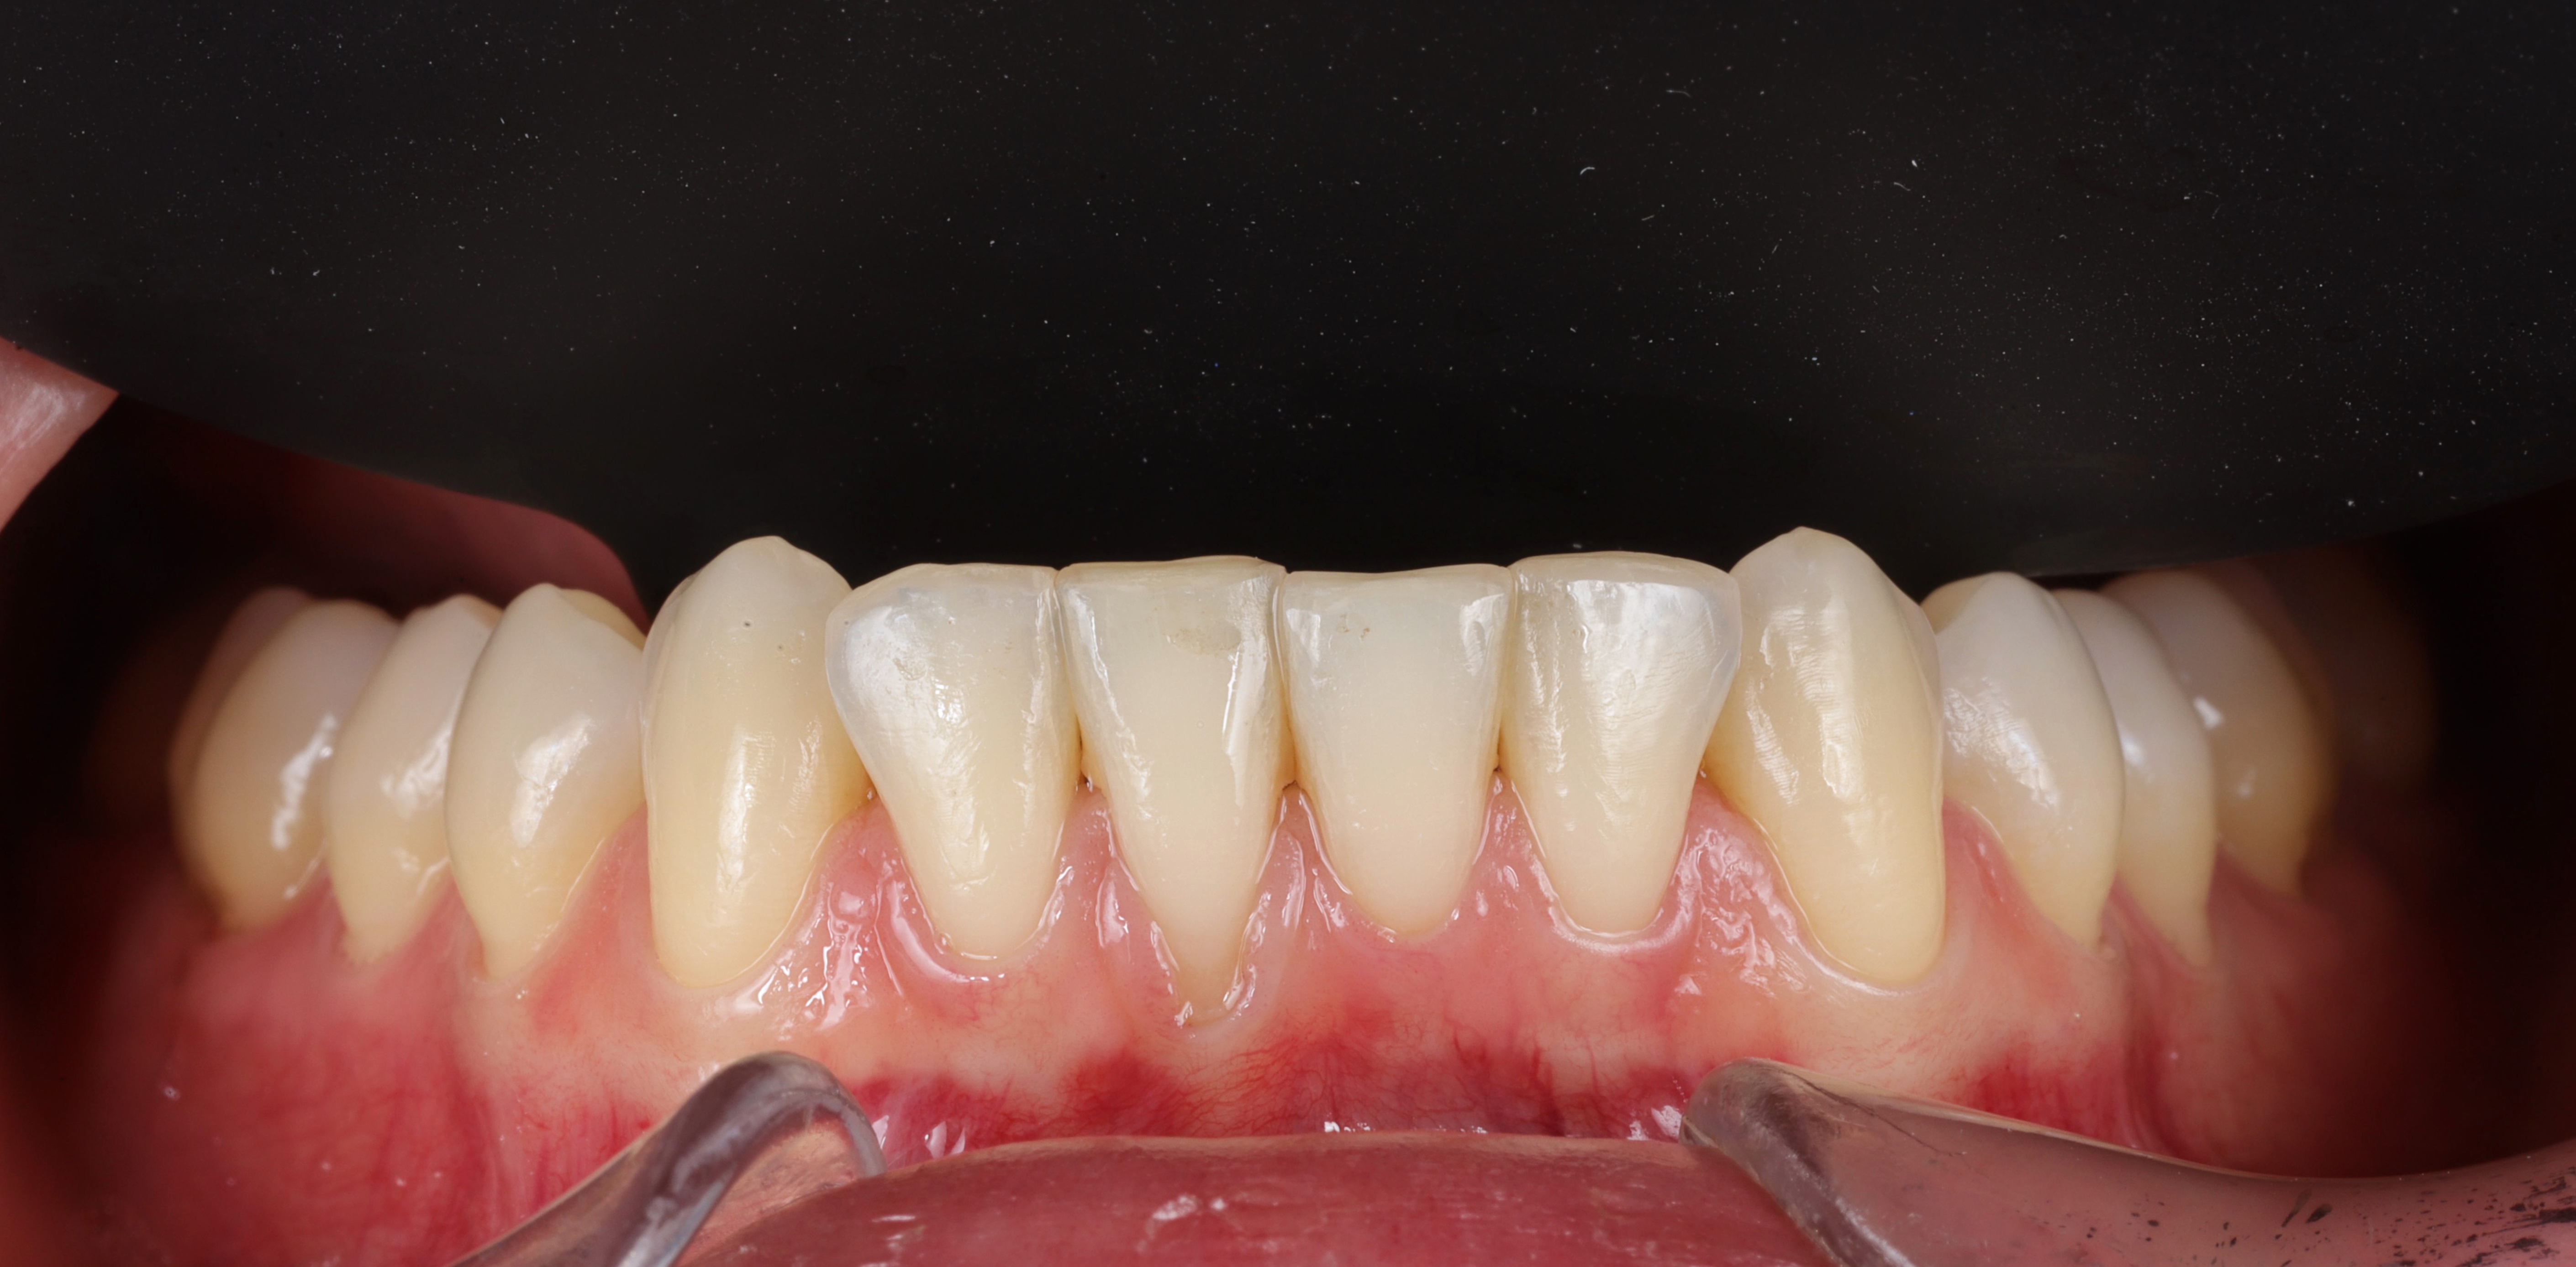

Gingival recession is the apical displacement of the gum margin, which exposes part of the tooth root.

Surgical root coverage aims to restore the gum level, reduce tooth sensitivity, protect the root from caries, and improve the overall aesthetics of the smile.

• Complete coverage of the exposed root and restoration of a harmonious gum line.

• Noticeable improvement in smile aesthetics, especially in the anterior region.